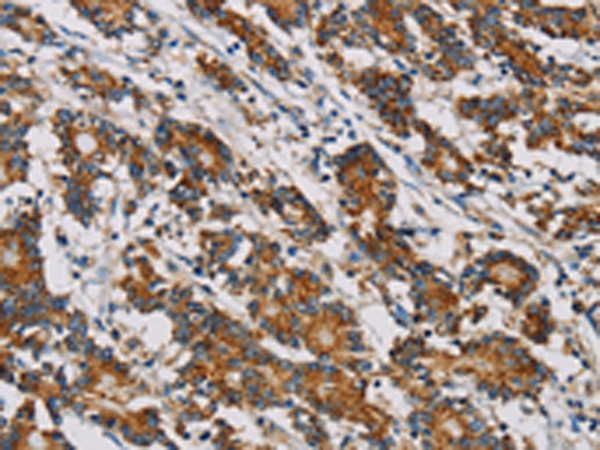

分类: 科研抗体货号: P08506别名: SPATA38应用: IHC反应种属: Human